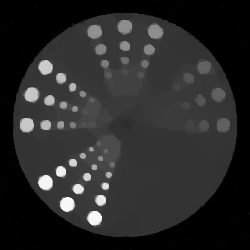

Fig. 2 on the left shows that the ergodic Bregman distance converges with rate as proven in Theorem 4.6. On the right we compare the deterministic PDHG with the randomized SPDHG and the algorithm of Pesquet&Repetti. It can be clearly seen that the proposed SPDHG converges much faster than both the algorithm of Pesquet&Repetti and the deterministic PDHG. Some example images are found in Fig. 2 after 5 epochs which again highlight the speed-up gained by randomization.

7.1 Non-Strongly Convex PET Reconstruction

In this example we consider positron emission tomography (PET) reconstruction with a total variation (TV) prior. The goal in PET imaging is to reconstruct the distribution of a radioactive tracer from its line integrals [31]. Let be the space of tracer distributions (images) and the data spaces where (200 views around the object) are subsets of indices with if and . All samplings in this example divide the views equidistantly. It is standard that PET reconstruction can be posed as the optimization problem Eq. 1 where the data fidelity term is given by the Kullback–Leibler divergence

Results